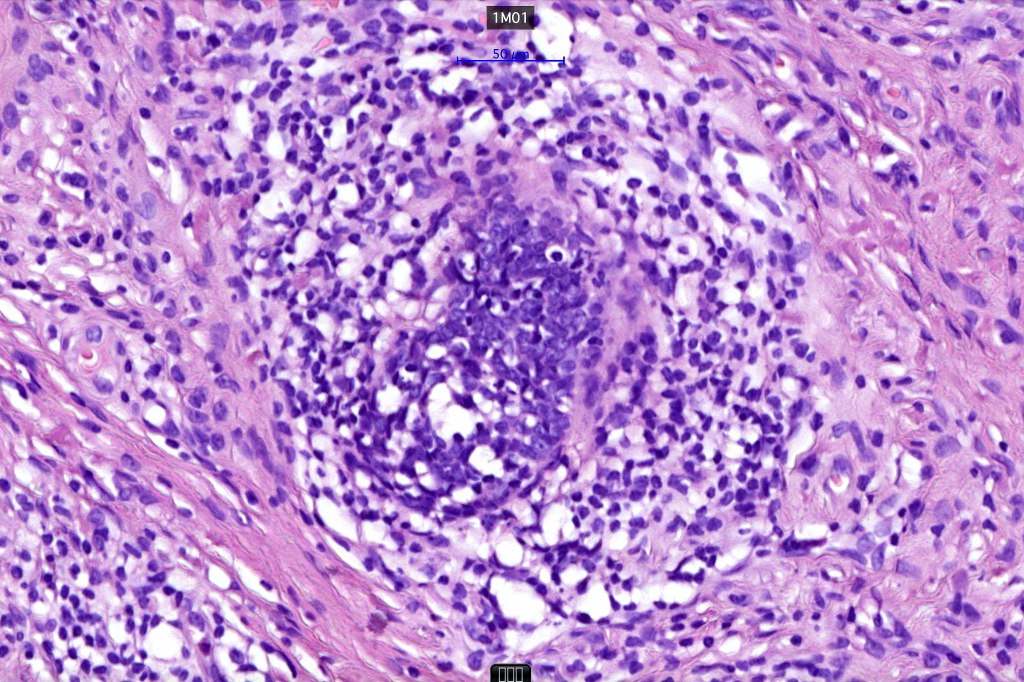

•The classical appearance consists of keratocysts & lobules of basaloid cells

•Perifollicular mesenchyme is always conspicuous and sometimes densely aggregated are seen indenting the baslaloid lobules (papillary mesenchymal bodies)

•Amyloid, foreign body granuloma formation to free keratin & calcification are variable features